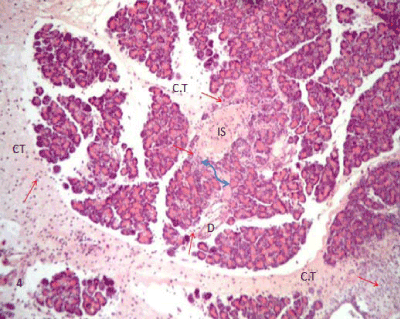

| Figure 4: A photomicrograph of rat pancreatic tissue of the diabetic group showing the indistinct boundary between the endocrine and exocrine part (blue arrow). Notice inflammatory cells (red arrows) infiltrating through connective tissue septae (CT), islet area (IS) and around the duct (D). (Hx&E x100). |